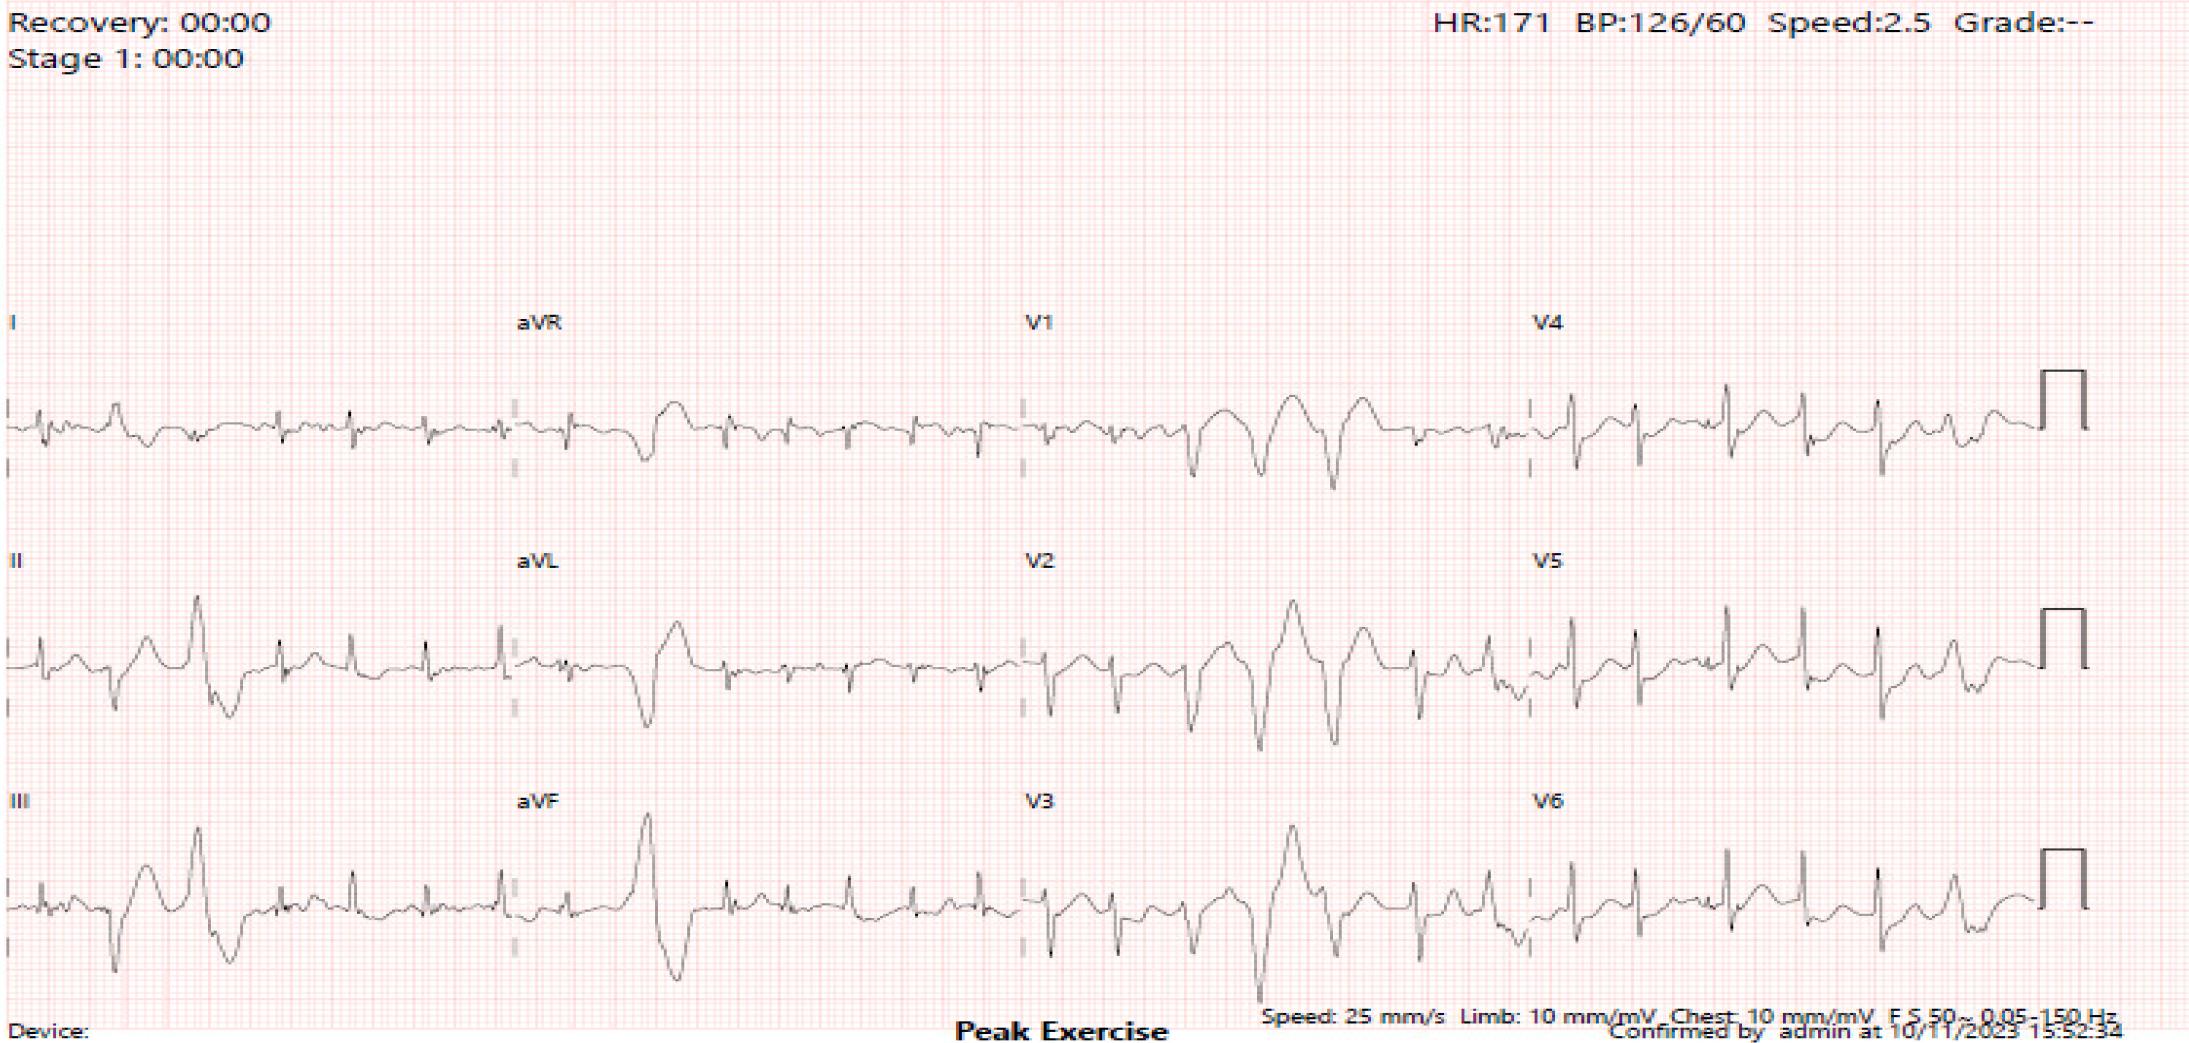

The same variant was later identified in our patient through predictive genetic testing. Our patient was reassessed in light of this new finding. An exercise test was conducted under bisoprolol where he exercised for 5 minutes under the Bruce protocol. He achieved a maximal HR of 171 bpm (105% of the predicted HR). PVCs were noted beyond 140 bpm, with 2 distinct morphologies. At 170 bpm, a bidirectional couplet was seen, followed shortly by an NSVT (3 beats at 170 bpm) (see Figure 3). The PVCs resolved quickly during recovery.

The second exercise tolerance test was performed under bisoprolol. The ECG strip recorded a bidirectional couplet and a 3-beat run at 170 bpm.